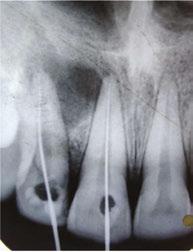

On intraoral examination, it was seen that the patient had mild discomfort on vertical percussion with respect to her upper maxillary left central and lateral incisors. The patient also complained of discomfort while palpating the mucobuccal fold corresponding to these incisors. An intraoral periapical radiograph showed the presence of large periapical radiolucency with irregular outline corresponding to upper maxillary left central and lateral incisors. Pulp sensibility tests (thermal and electric pulp tests) were then performed to determine the teeth responsible. As per the tests, it was concluded that only the maxillary central left and lateral incisors were the culprit.

The patient was reluctant for any sort of surgical procedure as she described an intense fear of any surgical intervention. Therefore, a non-surgical approach was chosen to treat this case of asymptomatic apical periodontitis associated with necrotic pulp. Access opening was carried out under proper aseptic conditions for both the upper central incisors. The working length was determined, and canals were shaped with K-files (Dentsply-Maillefer, Ballaigues, Switzerland) to an apical preparation of ISO size No. 80. During the preparation, the canals were irrigated with 2.5% NaOCl (Novo Dental Products Pvt. Ltd., Mumbai, India),

Figure 1: Preoperative image

Figures 2-4: 2. Working-length radiograph CBCT of the involved tooth. 3. Master cone radiograph. 4. Postoperative radiograph Figures 5 and 6: 1- year follow-up CBCT image